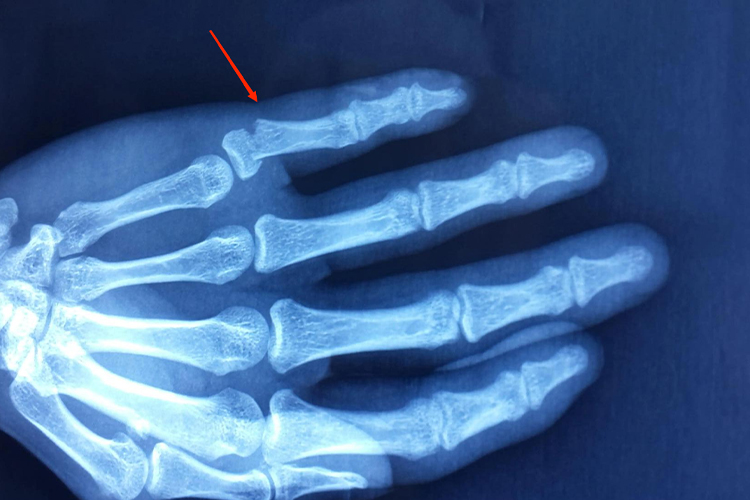

小拇指骨折主要表现为局部疼痛、肿胀和功能障碍,还可能伴有骨擦音等表现。

小拇指骨折时会出现疼痛、肿胀、指关节活动受限制等症状,在移动病指时疼痛加剧,伴明显压痛,还可能出现小拇指畸形、骨擦音和骨擦感等症状。

小拇指骨折通常为直接暴力引起,如硬物的砸伤、机器的绞伤、挤压伤等,多为横断形、斜形、螺旋形等。